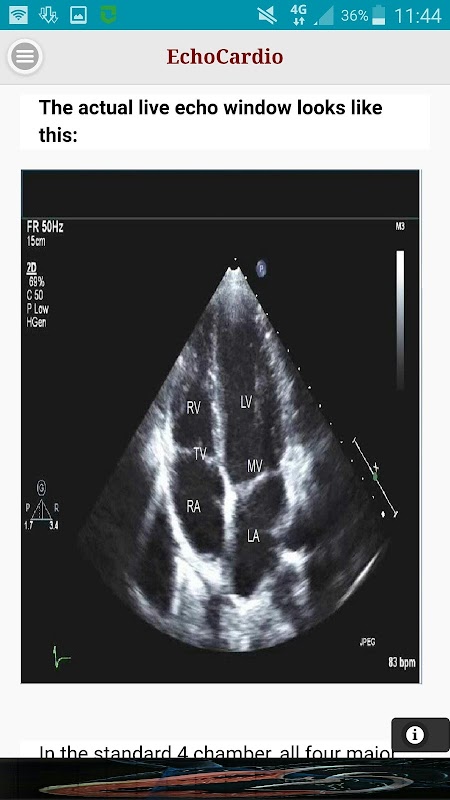

Transthoracale echocardiografie (TTE) is de meest uitgevoerde cardiale echo-onderzoek. Een hoge kwaliteit transthoracale echocardiogram kan snel worden uitgevoerd aan het bed en heeft de potentie om links en rechts systolische en diastolische functie, regionale wandbeweging, hartklepafwijkingen, en ziekten van het hartzakje uitgebreid kunnen evalueren.